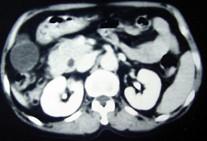

问题 男,55岁,中上腹隐痛多年,剑突下压痛,影像检查如图,最可能的诊断是 ( )

选项 A.十二肠溃疡 B.十二指肠憩室 C.十二指肠癌 D.十二指肠重复畸形 E.十二指肠穿孔

答案 B